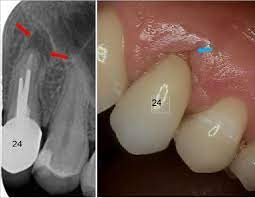

Wurzelkanalbehandlung Nach Bereits Erfolgter Wurzelspitzenresektion Zwp Online Das Nachrichtenportal Fur Die Dentalbranche